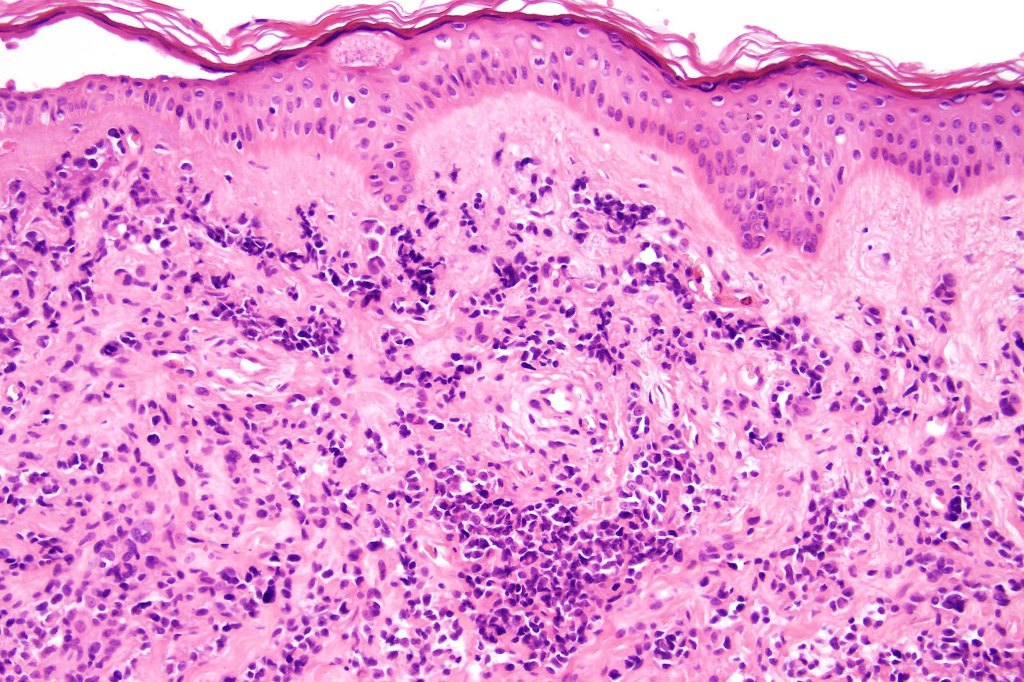

A rare variant of nevoid melanoma wherein the tumor cells have scant cytoplasm, and basophilic, hyperchromic nuclei mimicking type B nevus cells. Typically, the tumor cells are positive for S100, Mart-1 & HMB45. It is of no prognostic importance. It is one of the more often encountered melanoma variants in giant congenital nevi & can be mistaken for a congential nevus if the lesion is dismissed as benign at scanning magnification. In the absence of clinical history in metastatic lesions, the differential diagnoses of lymphoblastic leukemina/lymphoma, neuroendocrine carcinoma, small cell carcinoma, neuroblastoma, malignant perihperal nerve sheath tumor & Ewing’s sarcoma can be excluded with appropriate immunohistochemistry. Exceptionally small cell melanoma may express neuroendocrine markers